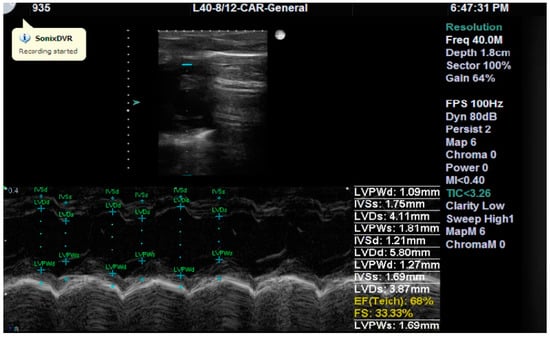

Cardiac structure and function were assessed by measuring the following parameters: interventricular septum systolic thickness (IVSs), left ventricular posterior wall diastolic thickness (LVPWd), left ventricular diameter in diastole (LVDd) and in systole (LVDs), left ventricular ejection fraction (LVEF), and left ventricular fractional shortening (LVFS) (Figure 2).

Figure 2. A representative echocardiographic image (parasternal short axis view at the level of the papillary muscles) showing the measurements taken on day two from a subject in the Mangiferin group for illustrative purposes.